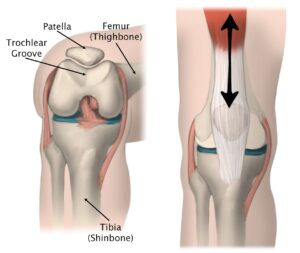

(Left) The patella rests in a small groove at the end of the femur called the trochlear groove.

(Right) As you bend and straighten your knee, the patella slides up and down within the groove.

Reproduced and adapted from The Body Almanac. American Academy of Orthopaedic Surgeons, 2003.